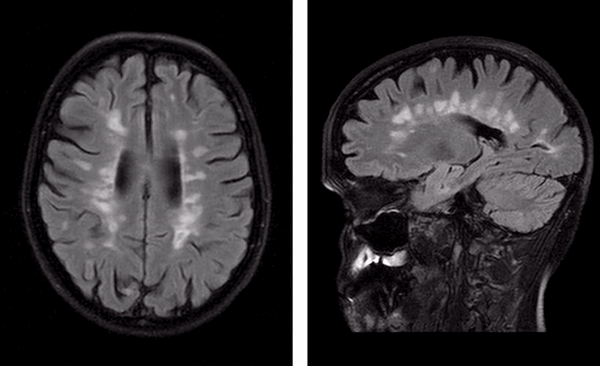

![Пальцы Доусона на МРТ]()

“Пальцы Доусона” на МР-томограммах в аксиальной (слева) и сагиттальной (справа) проекциях - выглядят на Т1 ВИ как светлые продолговатые очаги

Классическим признаком рассеянного склероза на МР-снимках головного мозга являются бляшки линейной формы, располагающиеся перпендикулярно боковым желудочкам. Их называют “пальцы Доусона”.

В спинном мозге очаги демиелинизации выглядят как удлиненные образования, распространяющиеся из центра на периферию с вовлечением в патологический процесс задних рогов.